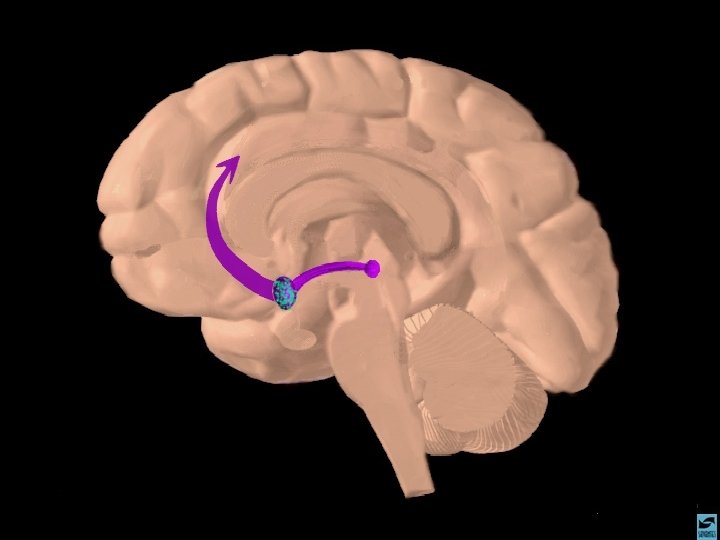

ANFETAMINAS E COCAÍNA EFEITOS CEREBRAIS: ATIVA OS SISTEMAS DOPAMINÉRGOS MESOLÍMBICOS E MESOCORTICAIS, INIBINDO A RECAPTAÇÃO DE DOPAMINA NOS TERMINAIS SINÁPTICOS E PROMOVENDO SUA LIBERAÇÃO NAS SINAPSES.